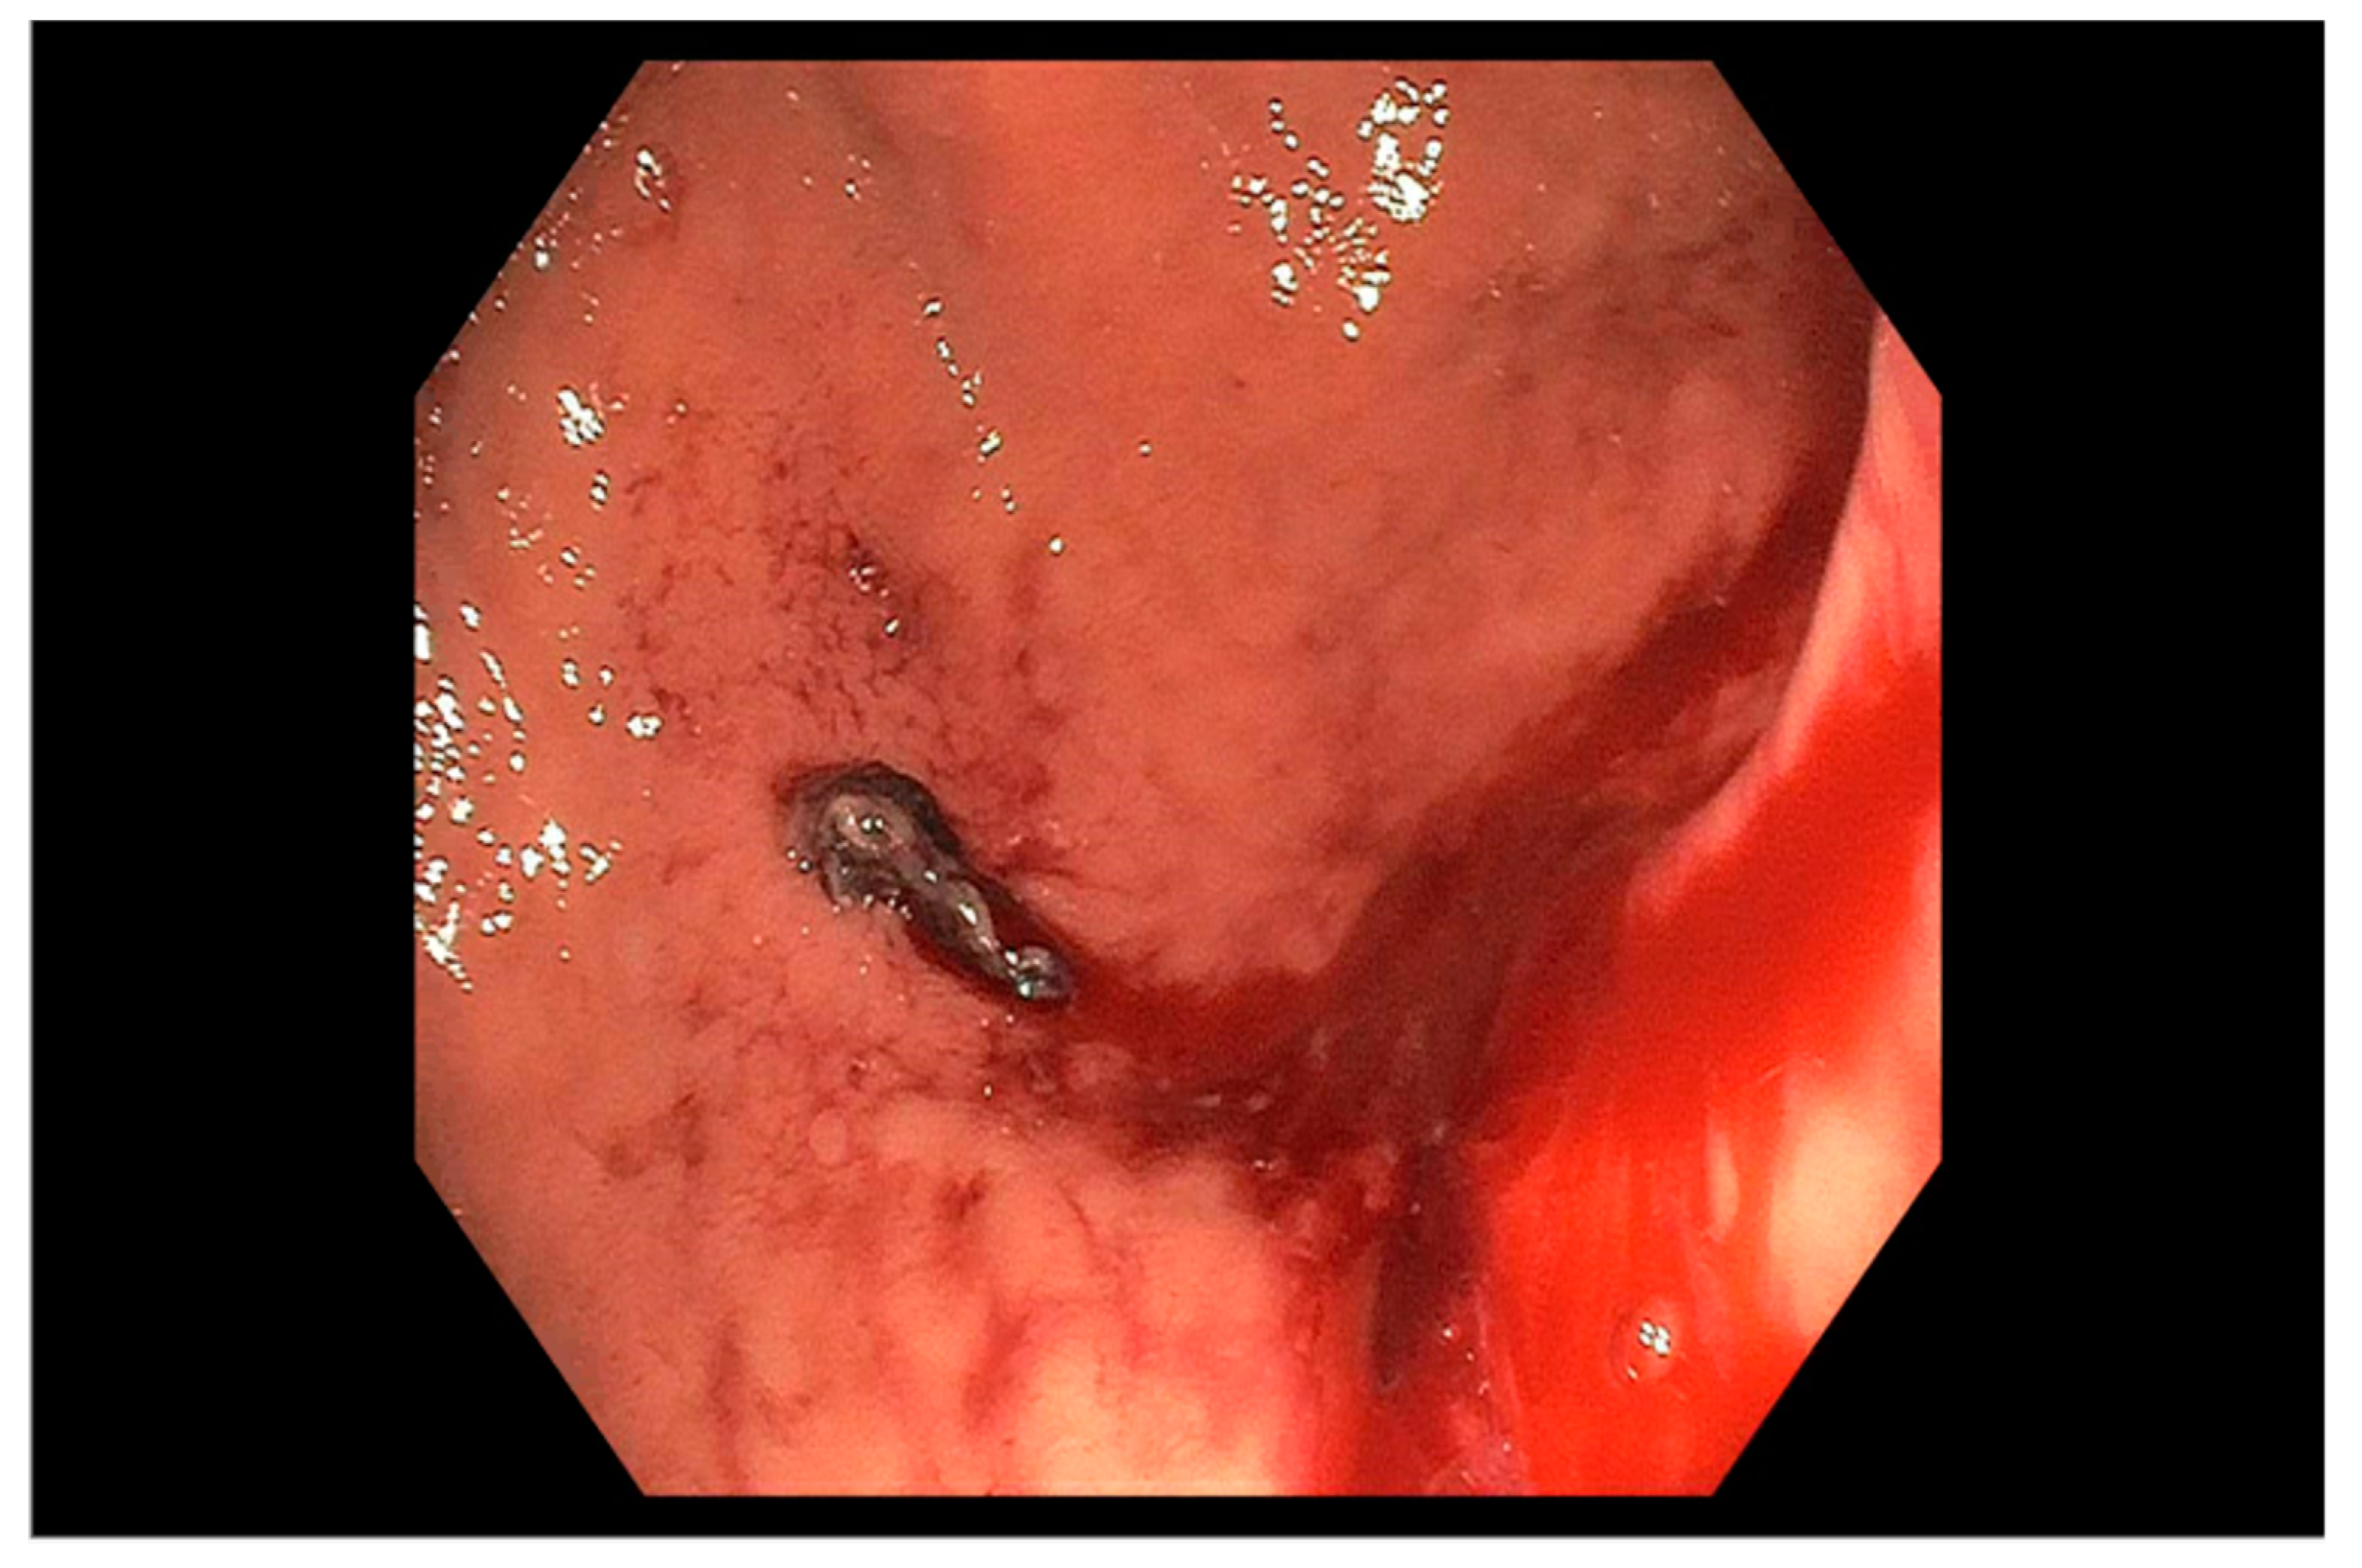

2.5. Endoscopic Therapy for Bleeding Peptic Ulcer Disease

2.6. Endoscopic Therapy for Other Non-Variceal Causes of Upper GI Bleeding